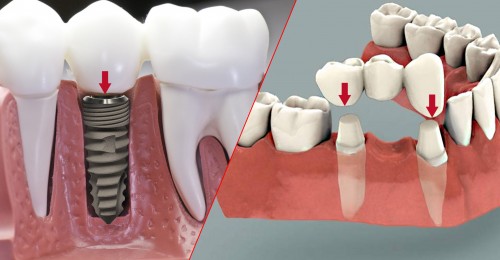

Cấy implant là phương pháp trồng răng tốt nhất hiện nay. Implant gồm có 3 phần, phần thứ nhất là chân răng, được cấy thẳng vào xương hàm thay thế chân răng mất. Phần thứ 2 là trụ phục hình abutment đó là phần kết nối với chân răng và nhô lên khỏi lợi để răng sứ bọc lên đó. Phần thứ 3 là răng sứ, sẽ là 1 chụp sứ hoặc hàm giả gắn lên abutment.

Khi mất một răng cửa bạn có thể lựa chọn các giải pháp phục hồi lại như làm hàm giả tháo lắp, làm cầu răng sứ, hoặc cấy chân implant. Trong đó cấy chân răng implant là giải pháp tốt nhất, bạn sẽ không phải can thiệp bào mòn 2 răng bên cạnh. Implant cũng ngăn ngừa được hiện tượng tiêu xương tiến triển khi mất răng.

Trước đây khi implant chưa phổ biến nếu bạn mất một hoặc một vài răng thì phương pháp phục hình tốt nhất là làm cầu răng sứ, tuy nhiên sau thời gian sử dụng thì cầu răng sứ bắt đầu bộc lộ những nhược điểm của nó và người dùng bắt đầu tìm phương án thay thế. Hiện nay khi implant đã rất phổ biến thì nhiều người muốn dùng nó để thay thế cầu răng. Vậy có thể thay thế cầu răng bằng implant hay không? Khi nào thì nên thay thế mời các bạn cùng theo dõi bài viết dưới đây của Nha Khoa Thùy Anh Thái Nguyên.

Khi bị mất răng lựa chọn phục hình bằng phương pháp làm cầu răng sứ hay cắm chân răng nhân tạo là việc khá khó khăn. Để có thể lựa chọn phương pháp phù hợp bạn cần có đủ thông tin để lựa chọn một cách đúng đắn và là người tiêu dùng dịch vụ thông thái.